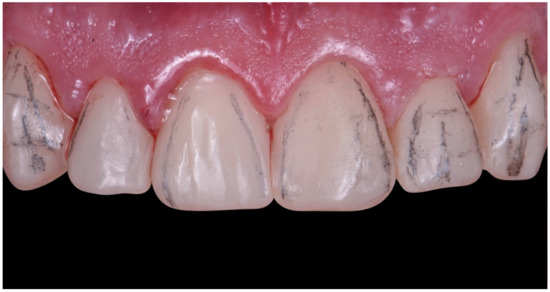

2.2. Restorative Phase